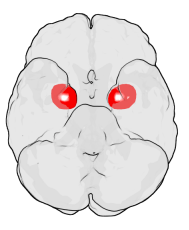

Las amígdalas del cerebro

A la entrada de la información del mundo externo, en las fauces del cerebro existe también a cada lado una formación con aspecto de almendra, inevitablemente llamada amigdala. Su extirpación daría lugar a una anestesia emocional.

Las amigdalas cerebrales analizan la relevancia biológica y social de los flujos de información de los sentidos. La información sensorial, después de dejar una copia en la amigdala, prosigue su curso hasta las áreas de procesamiento analítico y sesudo de la corteza. Si la amigdala detecta alguna señal sensorial etiquetada como relevante procede a activar la alerta y encender los motores del organismo para una respuesta eficaz.

La amigdala detecta información visual de caras emocionadas, olores y sonidos de lugares, rastros de una pareja potencial, cualquier señal que anuncie peligro, comida o ligue. Memoriza la relevancia de imágenes, olores y sonidos que acompañan a la realidad significativa y toma decisiones sin esperar a la opinión de las oficinas de lo intelectual, ganando un tiempo precioso para la supervivencia o el éxito.

Las amigdalas de lo estresados crónicos acaban engordando de tanto activarse, angostando el flujo informativo sensorial y derivándolo hacia el encendido preventivo de las alarmas.